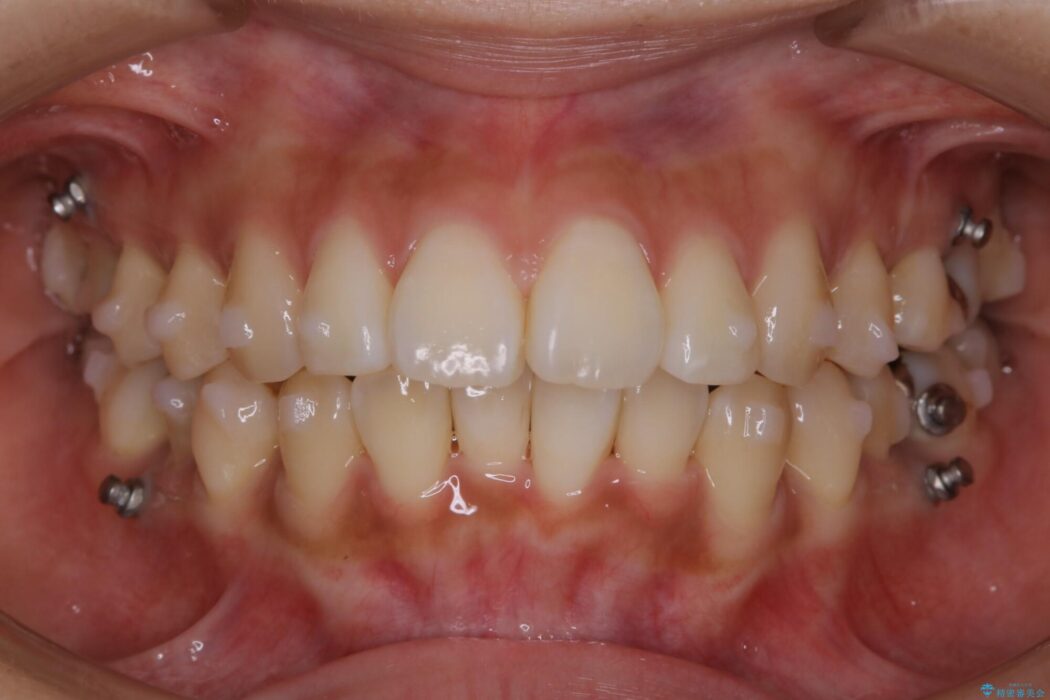

- 矯正装置:インビザライン+マイクロインプラント

よって患者様ご希望の非抜歯かつマウスピースでの矯正を行うために、最大量の臼歯の遠心移動をして歯列全体を奥へ引っ込める計画をご提案しました。

非抜歯での矯正治療

マウスピースにマイクロインプラントという補助装置を併用することで抜歯をせずとも歯列を整えるスペースを確保することができます。奥歯から順に移動させていくので前歯に変化が出るまでには時間がかかってしまいますが、健康な歯を抜歯することなく理想的な歯並びを手に入れることができます。